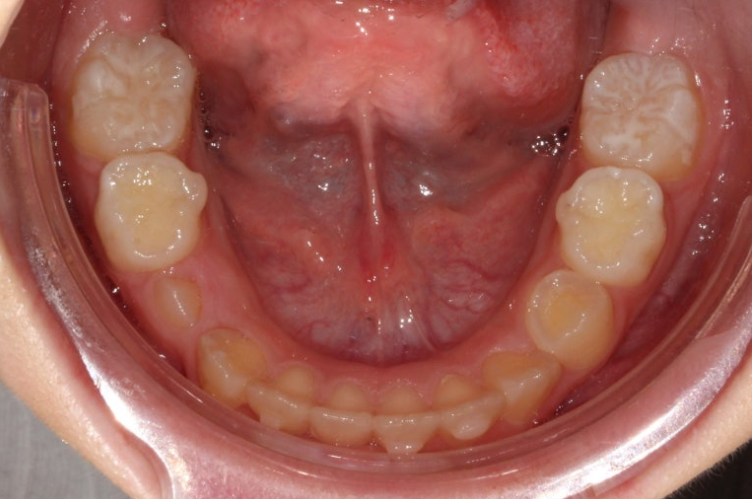

23.06

아랫니도 공간이 많이 부족합니다.

골격분석상 하악골 여성장을 동반한 무턱으로 진단되어 치료 목표는

-

악궁확장을 통한 덧니 해소

MA 기능으로 하악성장 유도

이 두가지가 되겠습니다.

손 엑스레이 성장판 분석한 결과 최대 성장기가 시작되는 시점이라 타이밍도 아주 좋습니다.

인비절라인 퍼스트로 권유드렸고 치료를 시작했습니다.